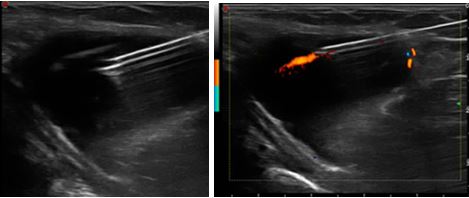

Enthesitis okozta UH elváltozások

B-mód UH vezérelt folyadékaspiráció, Power Doppler módú felvétel.